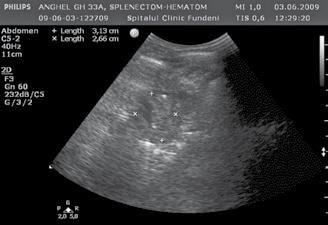

A opera sau a nu opera? Raspunsul ecografistului

Dr. Dan Adrian Stănescu 24